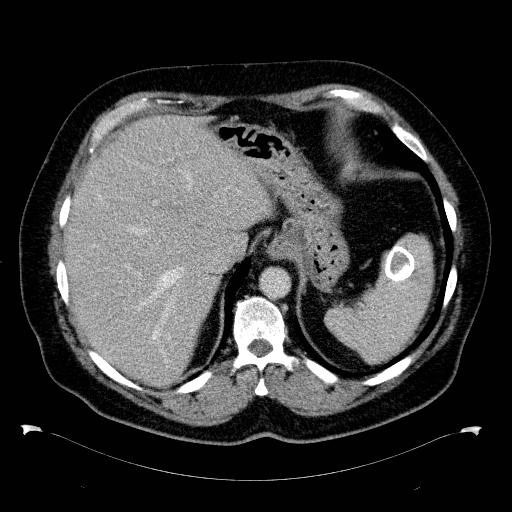

• Lách to (Splenomegaly)